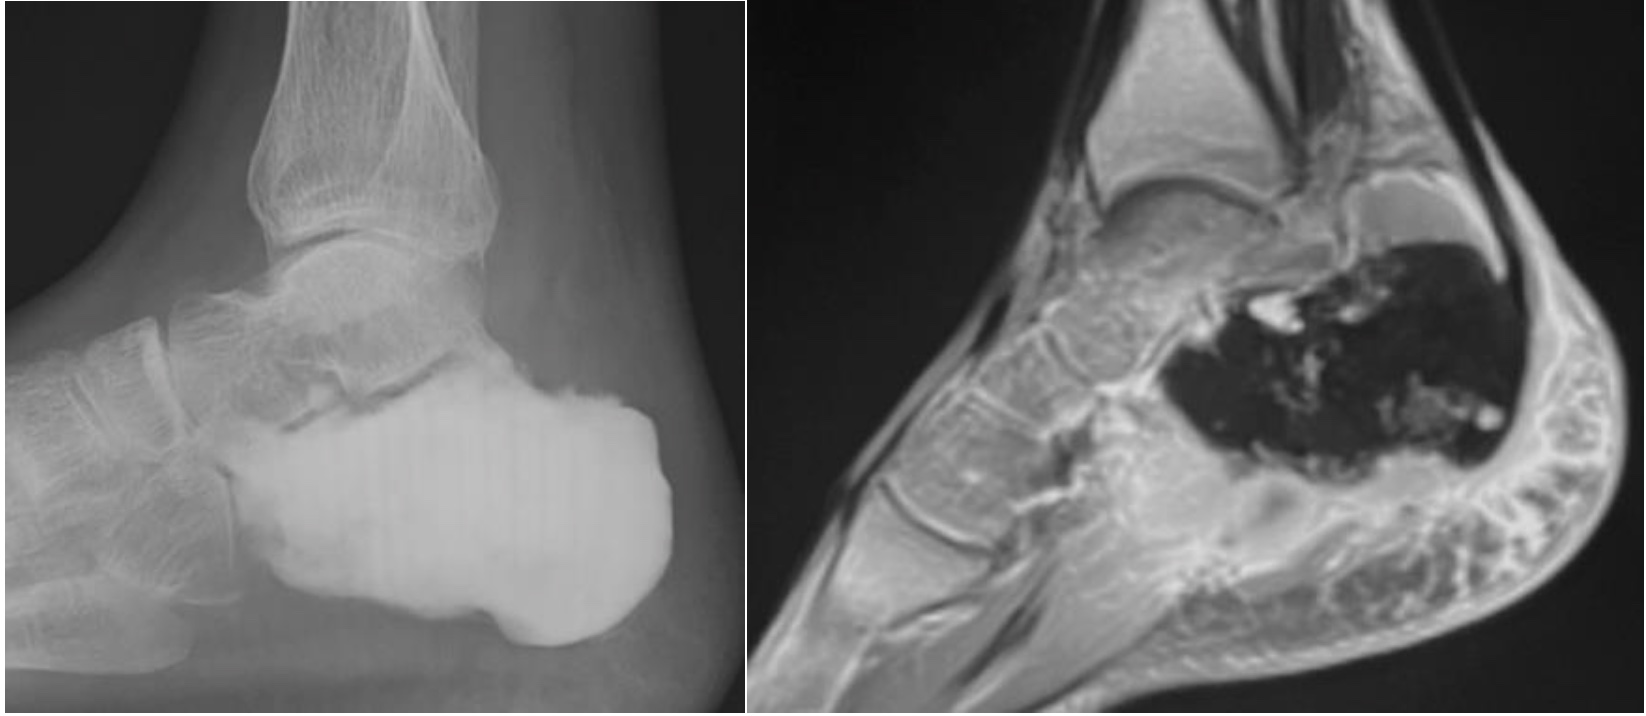

Intraosseous lipoma

- Typically occurs in the calcaneum

- Well-defined lucent lesion; may contain central calcification

- MRI diagnostic to confirm fatty matrix, seen as high T1 and T2 signal which supresses with fat saturation

Intraosseous lipoma calcaneum